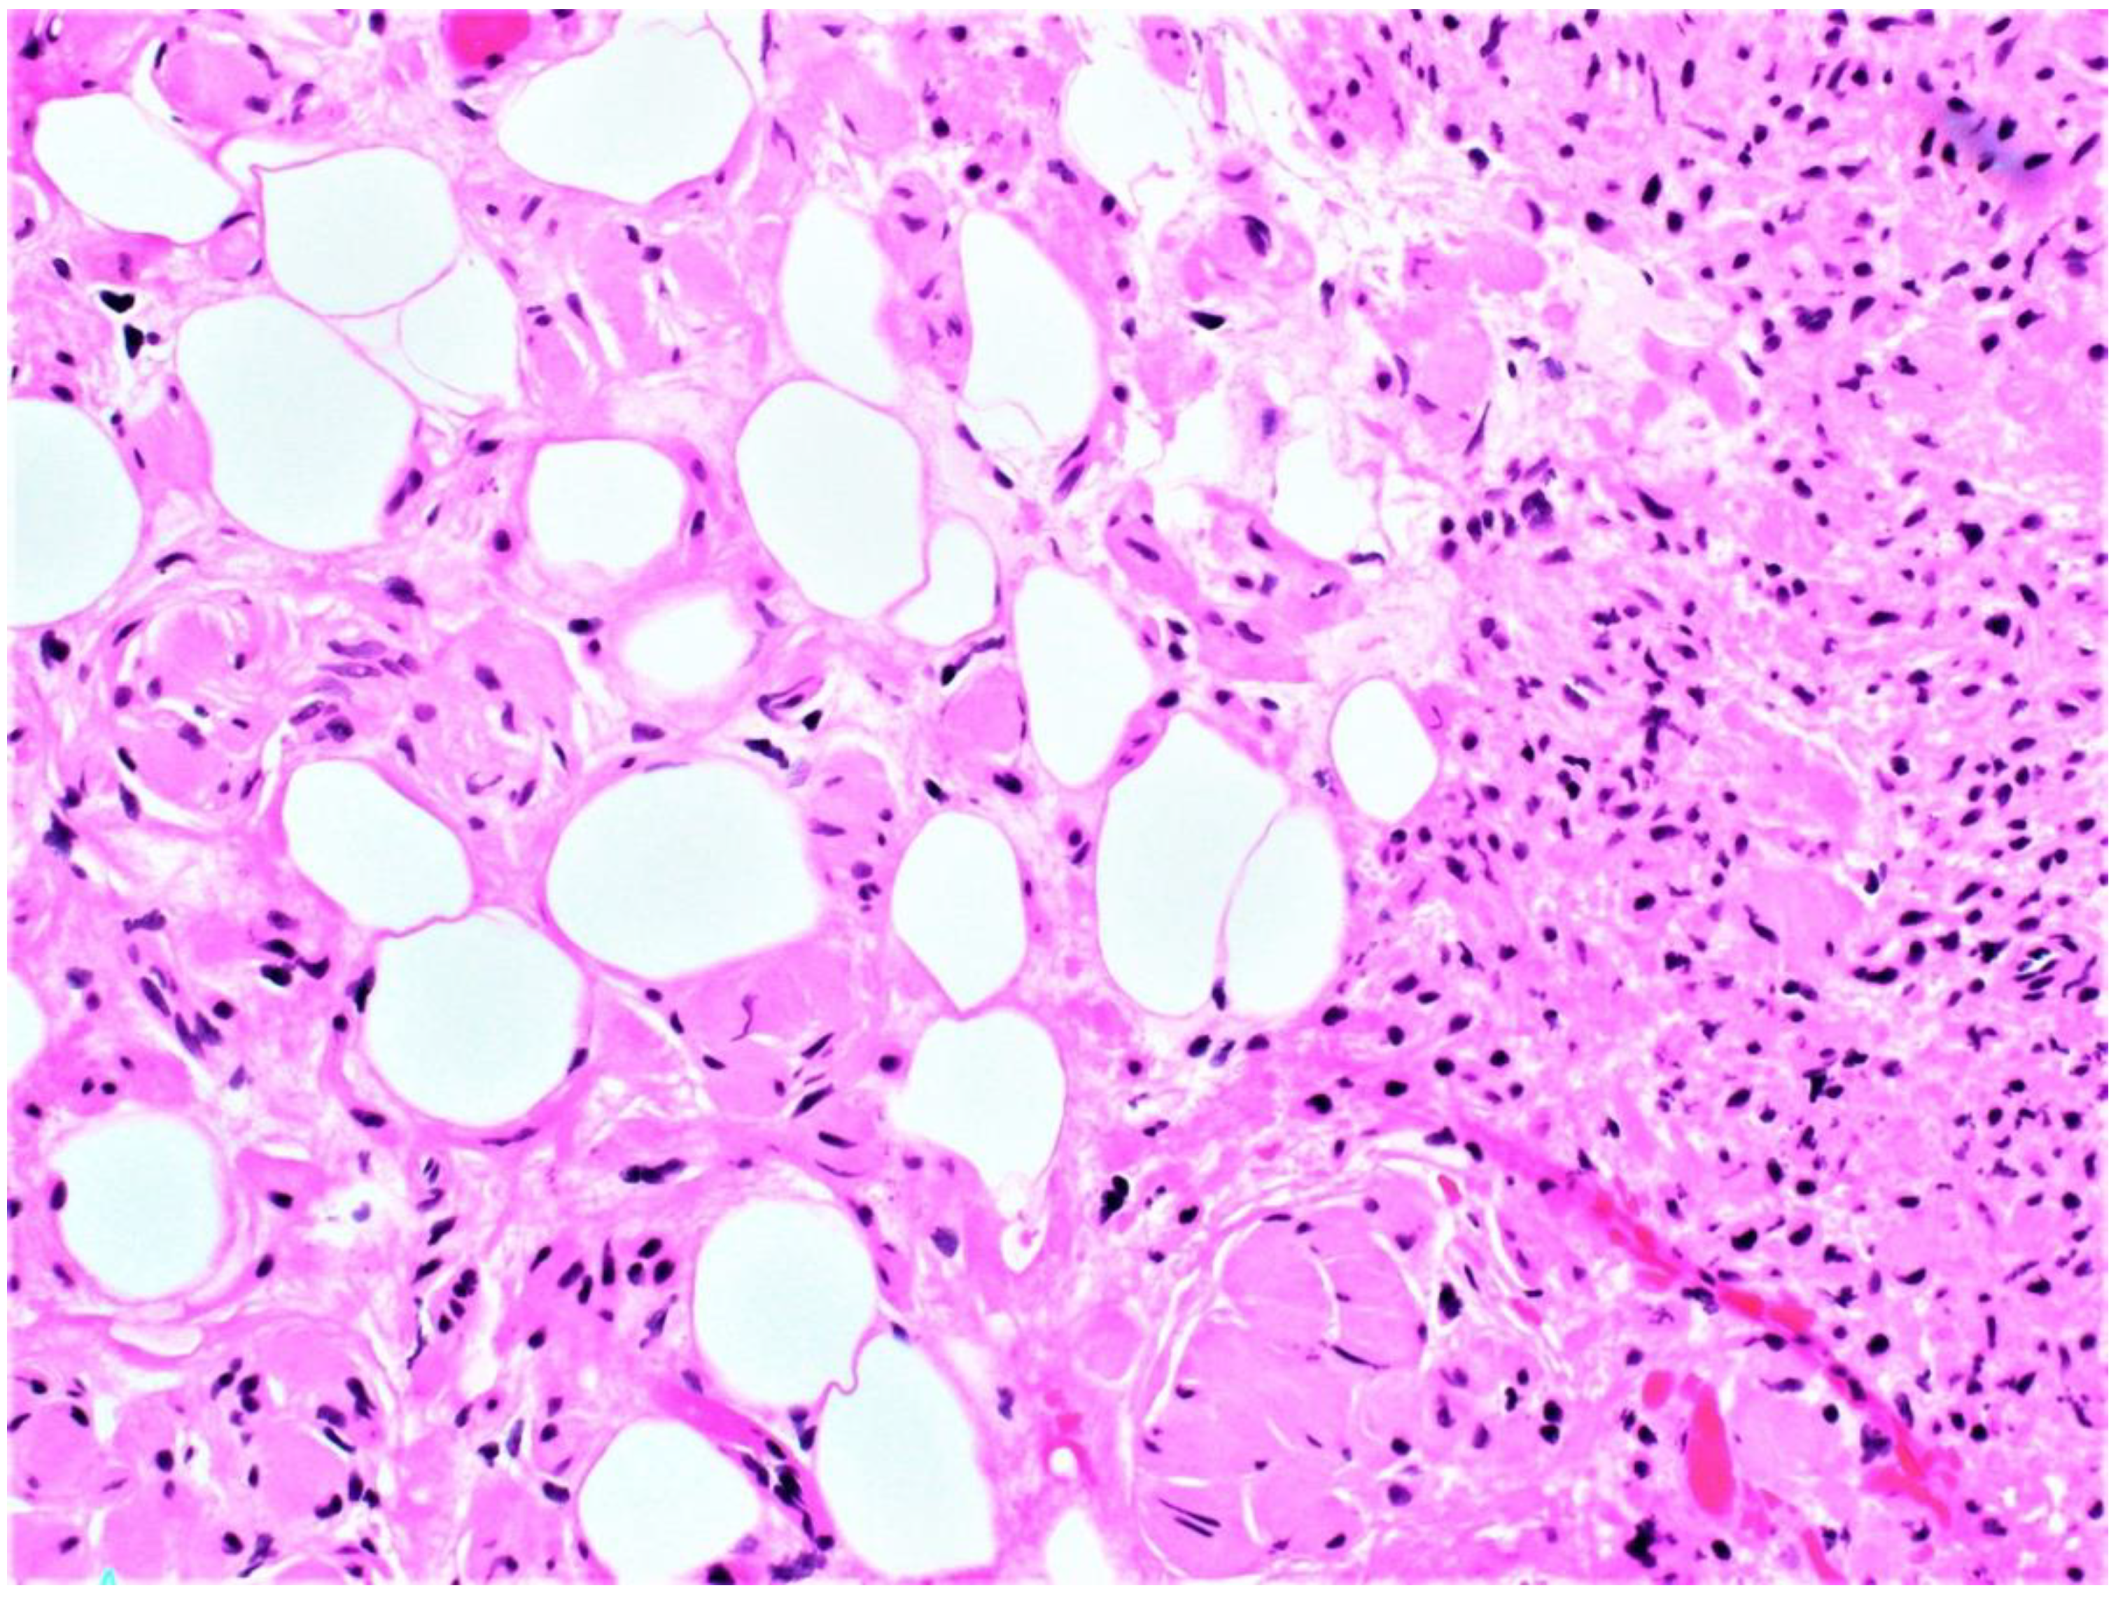

Microscopically, the lesion diffusely involved the skin dermis and subcutaneous soft tissue. Numerous vascularized areas were interspersed throughout the lesion, consistent with surgical findings. Loosely arranged spindle cells with hyperchromatic nuclei were arranged irregularly within the background of the collagenous stroma. Spindle cells had prominent infiltration of adipose tissue (Figure 1 and Figure 2) with the proliferation and entrapping of cutaneous adnexa structures (Figure 3).

Plexiform neurofibromas have varying presentations depending on the extension depth and location site. They arise from deeply located spinal nerve roots and have a highly ill-defined hyperpigmented and torturous appearance. Common symptoms include pain, numbness, and mass effect. Similar to diffuse neurofibroma, they can grow immensely, often surrounding multiple nerve fascicles [1,4]. The subtype is found in approximately 30-40 % of patients with NF1 and is considered pathognomonic for the hereditary disorder [1,4]. Diffuse neurofibroma is differentiated from plexiform neurofibroma subtypes by its defining characteristic of dermal and subcutaneous proliferation that irregularly entraps adnexa structures (Figure 3) and invades underlying adipose tissue (Figure 1 and Figure 2). Pseudomeissenerian bodies (Wagner-Meissner bodies), composed of eosinophilic fibrillary and whorled Schwann cells, are a unique characteristic feature of diffuse neurofibroma [1,10]. S100 is a sensitive but nonspecific marker for Schwann cells in neurofibromas (Figure 4). In diffuse neurofibromas, CD34 staining is fingerprint-like (Figure 5) because it stains admixed spindled fibroblasts in between collagen bundles [1]. Plexiform neurofibroma can be differentiated from diffuse neurofibroma due to its serpentine growth pattern, possible atypia, and irregular hypertrophic nerve fascicles [1,4]. The patient’s clinical presentation of headache and tenderness is more in line with a plexiform neurofibroma. However, histopathological findings were consistent with a diffuse neurofibroma as microscopic examination did not reveal nuclear atypia or hypertrophic nerve fascicles. Additionally, she did not exhibit the usual alternative traits associated with NF1. The neurofibroma subtypes are microscopically similar because they comprise loosely arranged ovoid to spindle cells with hyperchromatic buckled to wavy nuclei within a background of myoxid to pale pink collagenous matrix [1,8,9].

Figure 1. Low-power microscopic examination showing proliferation of spindle cells and adipose tissue infiltration.